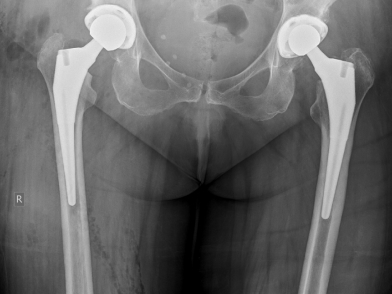

Η ριζική θεραπεία της οστεοαρθρίτιδας του ισχίου είναι η ολική αρθροπλαστική του ισχίου, δηλαδή η αντικατάσταση της άρθρωσης από τεχνητή.